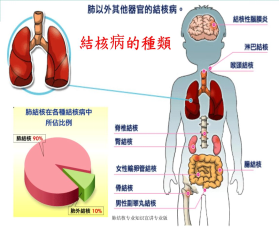

结核病是由结核分枝杆菌引起的传染病,可侵及许多脏器,如:肺结核、淋巴结结核、肠结核、肾结核、子宫内膜结核、输卵管结核、皮肤结核、骨关节结核、脑膜结核等,其中肺结核最为常见。